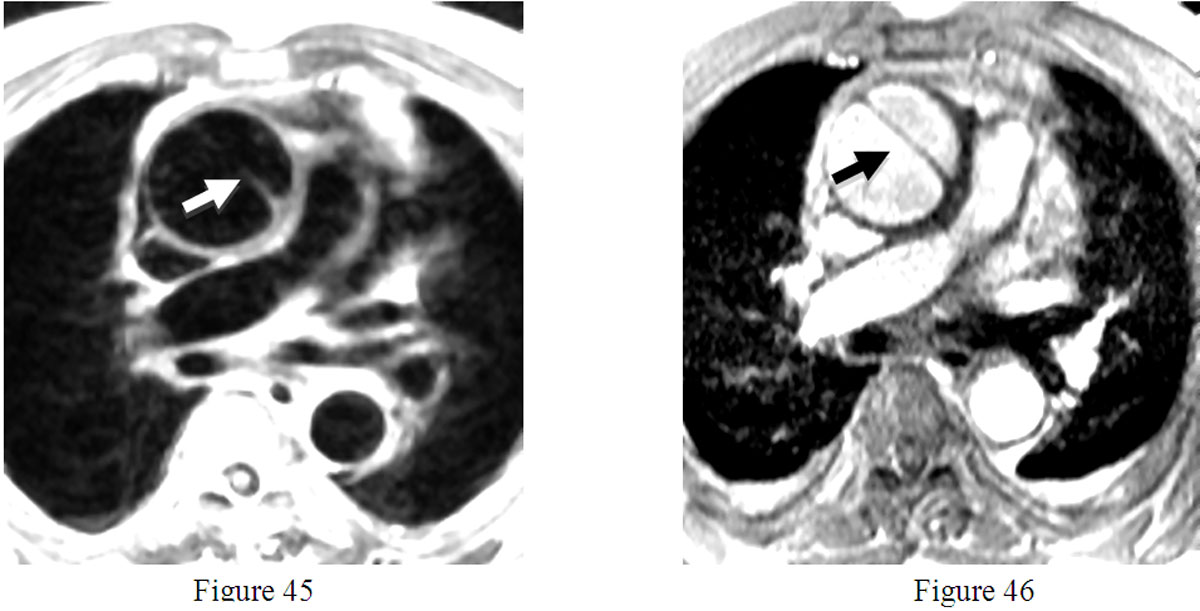

L’examen comporte habituellement la réalisation de coupes dans plusieurs plans de l’espace, utilisant des techniques « sang noir » et « sang blanc ».Avec les premières (figure 45), les cavités du cœur et des vaisseaux, noires, contrastent spontanément avec la paroi qui apparaît grise. Avec les secondes (figure 46) qui comportent notamment les images dynamiques en ciné-IRM, le sang est blanc et contraste avec les parois qui sont grises. (clichés présentés : coupes petit axe avec deux modes d’imagerie d’une dissection de l’aorte ascendante : flèches).

Figures 45 et 46 : Sémiologie de base des images